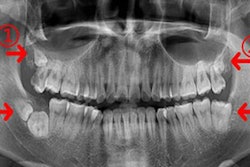

X-Panel 1615 is available in two models. X-Panel 1615s features built-in functions for extra image stability during long fluoroscopy procedures and is designed for use with surgical C-arms. X-Panel 1615d can scan full frames at speeds up to 66 frames per second, and it is optimized for dental cone-beam CT (CBCT) and panoramic imaging applications.